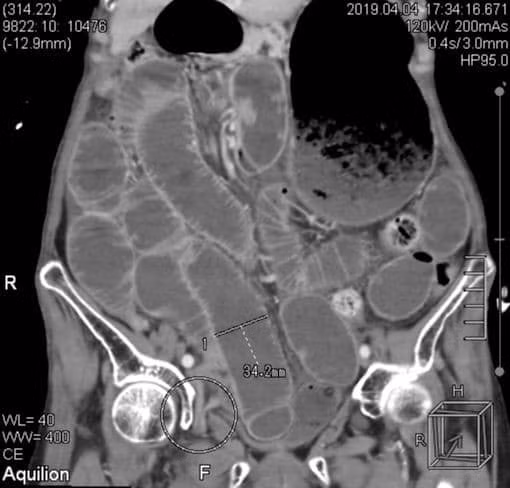

| Vị trí bịt ruột gây tắc hoại tử hiếm gặp của bệnh nhân |

Qua thăm khám, CT bụng, các bác sĩ xác định cụ N. bị tắc ruột, nhiễm trùng nặng. Nguyên nhân là do một phần quai ruột non chui vào lỗ bịt, gây tắc và hoại tử ruột.